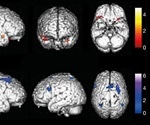

Brain metabolic changes associated with loss of smell in COVID-19